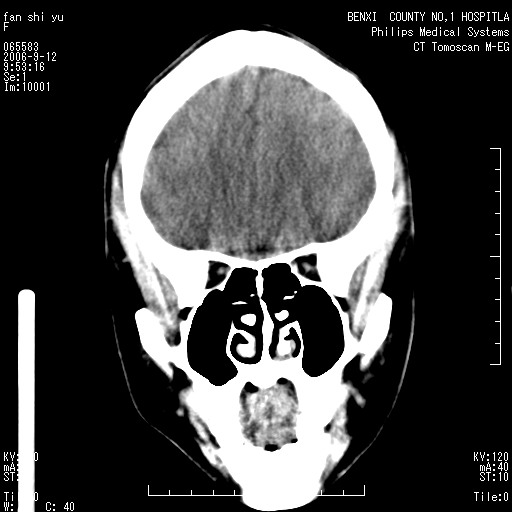

标题: CT4607:看看这个头颅冠状位。

女,22岁,自觉头顶部质硬包块.

巨大蛛网膜粒压迹。

为何没有轴位扫描 考虑蛛网膜囊肿压迹 可mr检查确诊

考虑:蛛网膜囊肿压迹 建议作mri检查确诊

蛛网膜粒压迹应该没什么疑义。